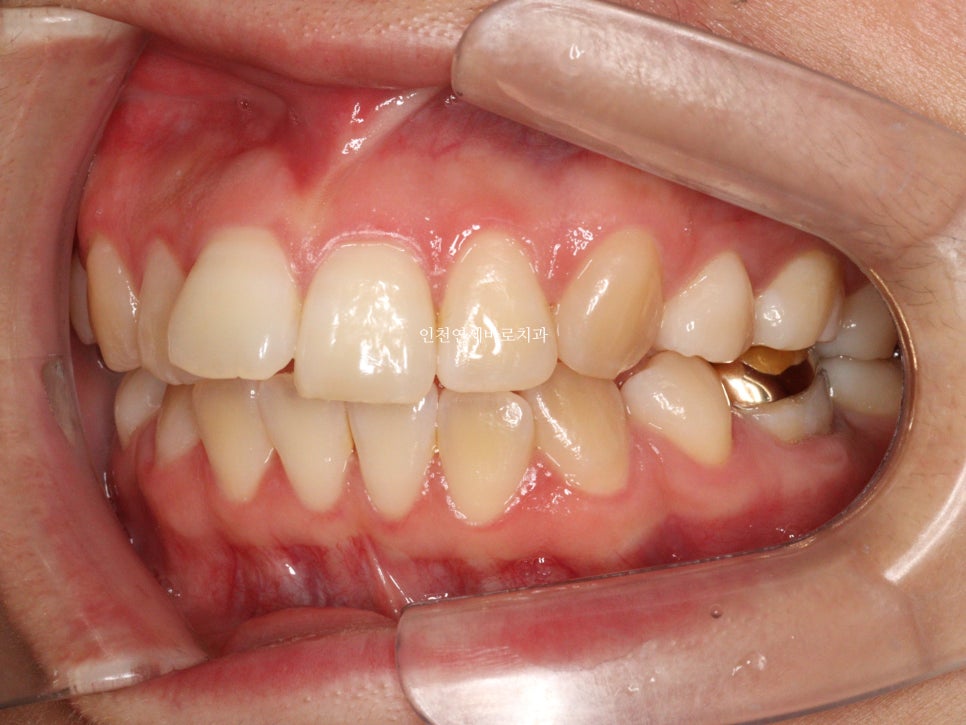

변화모습입니다.

약 3개월의 변화모습입니다.

그리고 치료가 마무리 된 후의 모습입니다.

위 환자분의 재교정 치료기간은 약 7개월입니다.